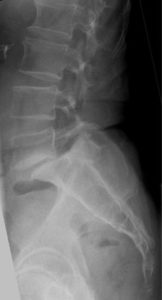

Lumbar Spine

The Lumbar vertebrae are the largest segments of the movable part of the vertebral column. Consisting of five vertebrae, the lumbar region of the spine is the main source of body motion and supports most of the body’s weight. It is commonly associated with the “lower back” region of the body.